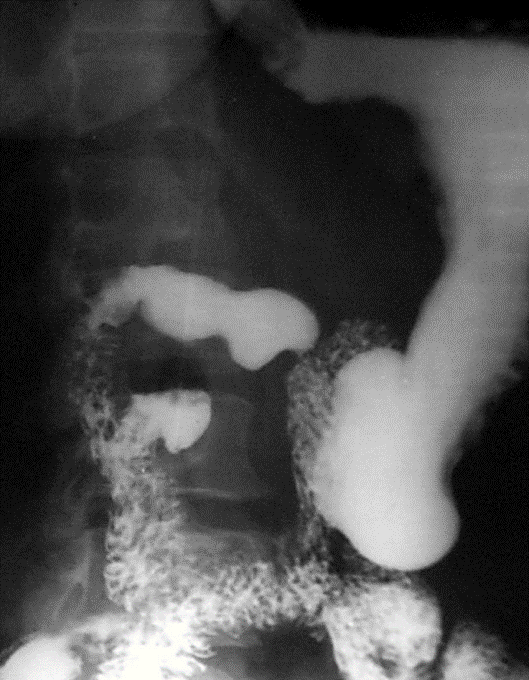

Назовите ведущий рентгенологический синдром на данной рентгенограмме// Нарушение рельефа слизистой// Дефект наполнения просвета кишечника// Ограниченное расширение просвета кишечника// +Ограниченное сужение просвета кишечника// Тотальное сужение просвета кишечника

Поставьте заключение по данной// рентгенограмме// Блюдцеобразный рак желудка// +Язвенная болезнь желудка// Болезнь Гришпрунга// Дивертикулез кишечника// Полип желудка

Назовите фазу контрастирования кишечника// Фаза одномоментного двойного контрастирования// Фаза спадения// Фаза тугого контрастирования// +Фаза рельефа// Фаза двойного контрастирования

Назовите ведущий симптом на данной рентгенограмме// Нарушение рельефа слизистой// Дефект наполнения просвета кишечника// Ограниченное расширение просвета кишечника// +Ограниченное сужение просвета кишечника// Тотальное сужение просвета кишечника